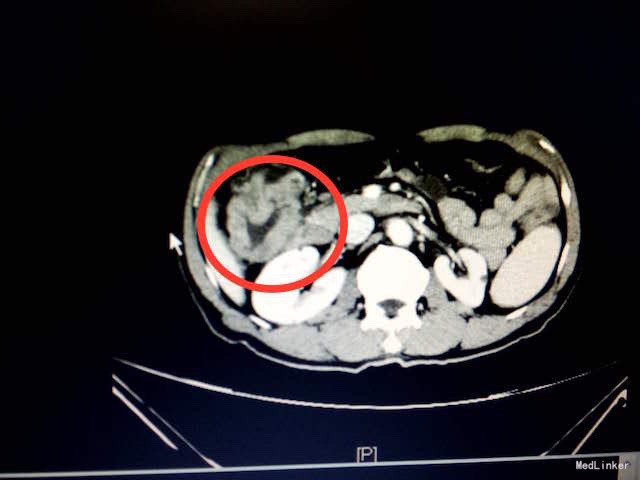

查体:消瘦体型,心肺查体阴性。腹软,右上腹深压痛,无反跳痛,未触及包块,肠鸣音正常。 辅助检查:入院血常规、生化、肝肾功、凝血、传染病未见明显异常。胃肠肿瘤指标正常。大便隐血试验(+)。腹部CT结果:结肠肝曲肠壁局部明显增厚,增强扫描强化明显,考虑恶性肿瘤,累及浆膜层(如下图所示)。